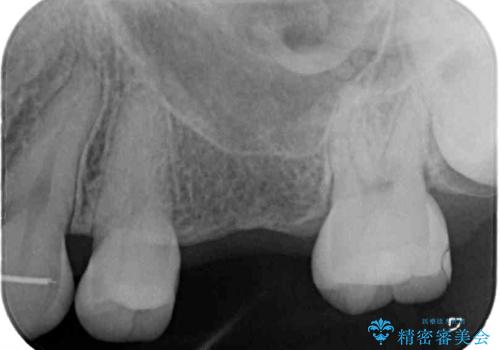

また、上顎臼歯は虫歯により抜歯されてから放置されている状態でした。

舌のトレーニングをしっかりと行っていただきながらワイヤー装置により矯正治療を行い、途中でインプラントを埋入し、矯正治療後に補綴治療を行うこととしました。